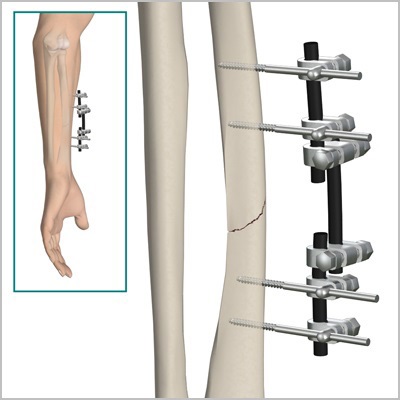

indicație absolută pentru intervențiile chirurgicale au fost fracturi deschise. In astfel de cazuri, primul pas vom stabiliza fracturi folosind dispozitive de fixare externe.

Pentru vindecarea rănilor, un al doilea pas, vom elimina dispozitivul și să producă o tijă de fixare finală intramedular sau placă. În această abordare, fixarea finală este realizată după vindecarea fracturii după un prejudiciu, astfel probabilitatea complicațiilor septice infecțioase este redus semnificativ.

Operațiuni antebrațului este extrem de periculos din punct de vedere al daunelor de vase și nervi. Rezultatul acestor complicații pot fi tulburări de mișcare ireversibile și sensibilitate în domeniul periilor. Posibilitatea de a dezvolta astfel de complicații impune o mare responsabilitate a chirurgului în timpul planificarea și desfășurarea operațiunilor în aceste fracturi.